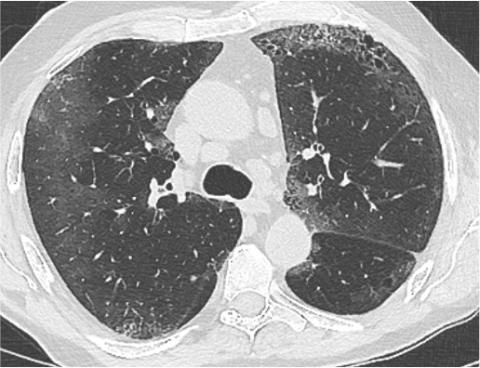

Entraînez-vous à lire des radios en vous appuyant sur des corrélations radio-scanner! Découvrez le site d'auto-apprentissage de la radiographie thoracique